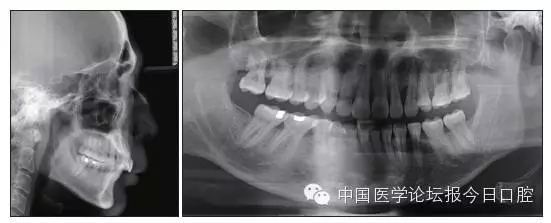

全口曲面體層片(圖3)顯示,患者全牙列牙槽骨吸收;根尖片(圖4)示11近中牙槽骨角形吸收已達根尖1/3,21牙槽骨嵴頂吸收至根1/2,23牙槽骨近中骨板角形吸收至根1/2。磨牙區(qū)骨嵴頂吸收3mm。治療前頭顱側位片見圖3,治療前ODS模型見圖5。

圖3 治療前頭顱側位片及曲面體層片